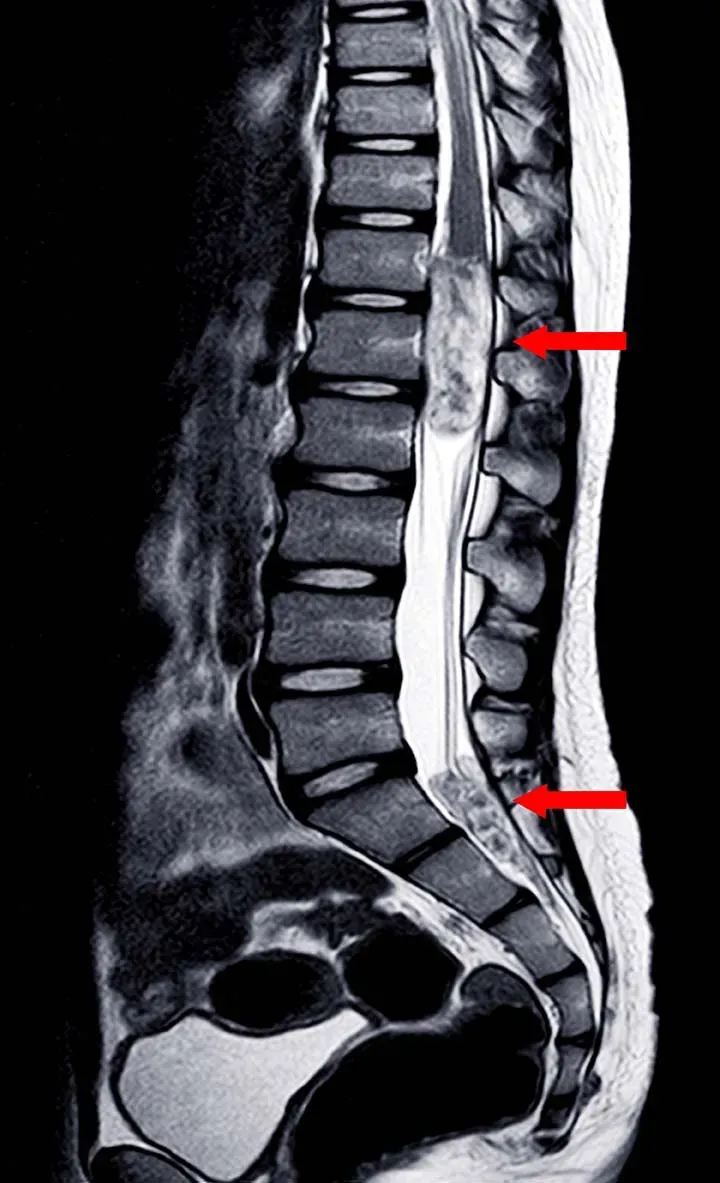

- Magnetic Resonance Imaging (MRI)

The goal is to accurately define the type, extent, and relationship of the tumor to neural structures.